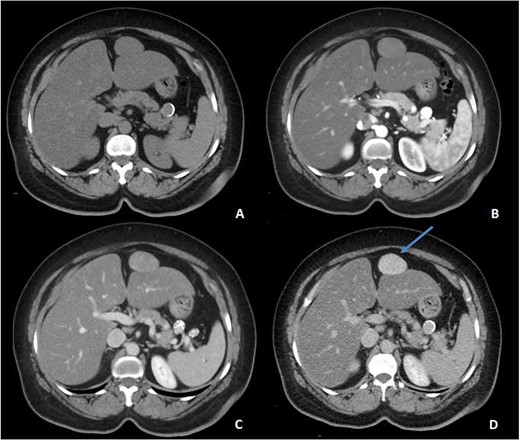

An ultrasound of the abdomen revealed a homogonous hypoechoic lesion anterior to the left hepatic lobe (Fig. 1). Color doppler images (not shown) shows internal blood flow. A subsequent abdominal computed tomography (CT) scan was done, and it revealed a 4.9 × 5.5 cm well-defined, homogeneous, progressively enhancing mass anterior to the left hepatic lobe (Fig. 2). The differential diagnoses included desmoid tumor, leiomyoma, hemangioma and gastrointestinal stromal tumor (GIST). EGD and CT colonography were done and both came back negative for synchronous lesion.

Pre-contrast (A), Arterial (B), Porto-venous (C) and Delayed (D) images of contrast enhanced CT demonstrating a well-defined, homogeneous, progressively enhancing mass anterior to the left hepatic lobe, with homogeneous delayed images (blue arrow). Incidental hepatic steatosis and a small splenic artery aneurysm are present.